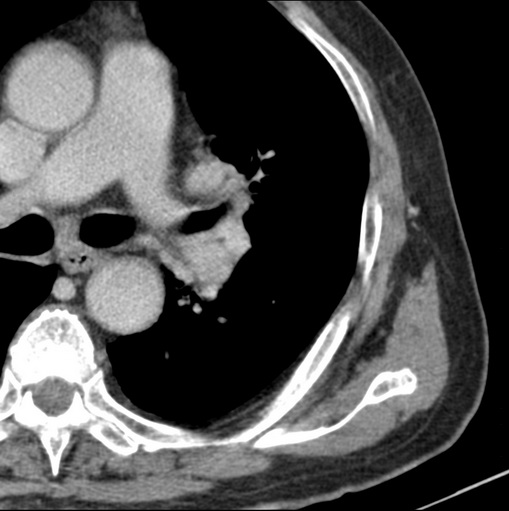

标题: CT25434:胸部CT增强扫描

男性患者 81岁 咳嗽 咳痰 咯血

肿块贴近左肺门,包绕左上肺动脉,形态不规则。肿块增强扫描中度强化。纵膈内主动脉弓左旁间隙、气管隆突前、下间隙见多枚淋巴结影。综上考虑左侧中央型肺癌可能性大。图片没有完整上传,尤其是左肺上叶支气管分支层面没有上传,因此不好判断是叶支气管中断还是段支气管中断。另外,下图红色部分所示是“黏液支气管征”吗?